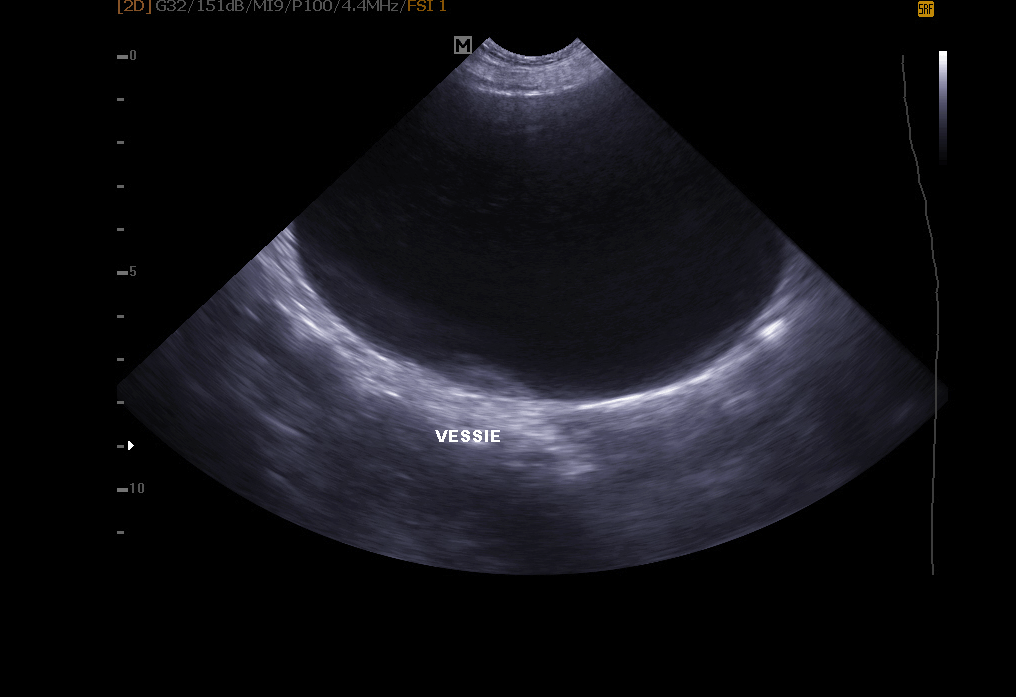

Abdominal ultrasound:

Abdominal ultrasound: it allows exploration of the bladder (search for stones, polyps, tumor), kidneys, spleen, liver, pancreas and other abdominal organs.